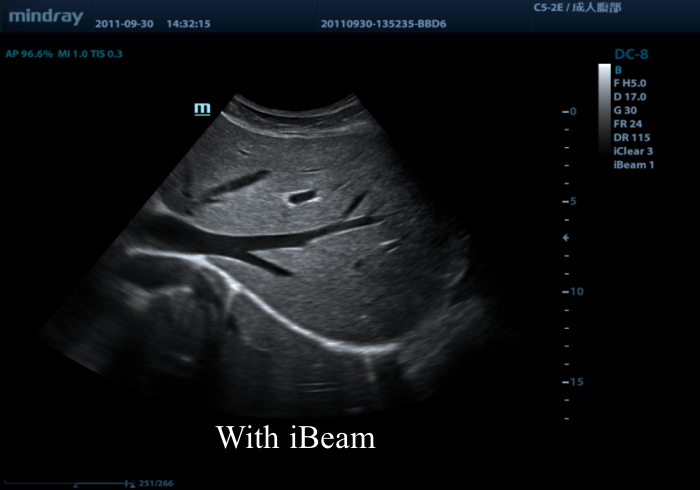

Предлагаем вам ознакомиться с примером применения данной технологии. Изображения выполнены на приборе Mindray DC-8, на верхнем изображении режим iBeam (компаундинг) отключен, а на нижнем включен на первую ступень регулировки (3 луча).